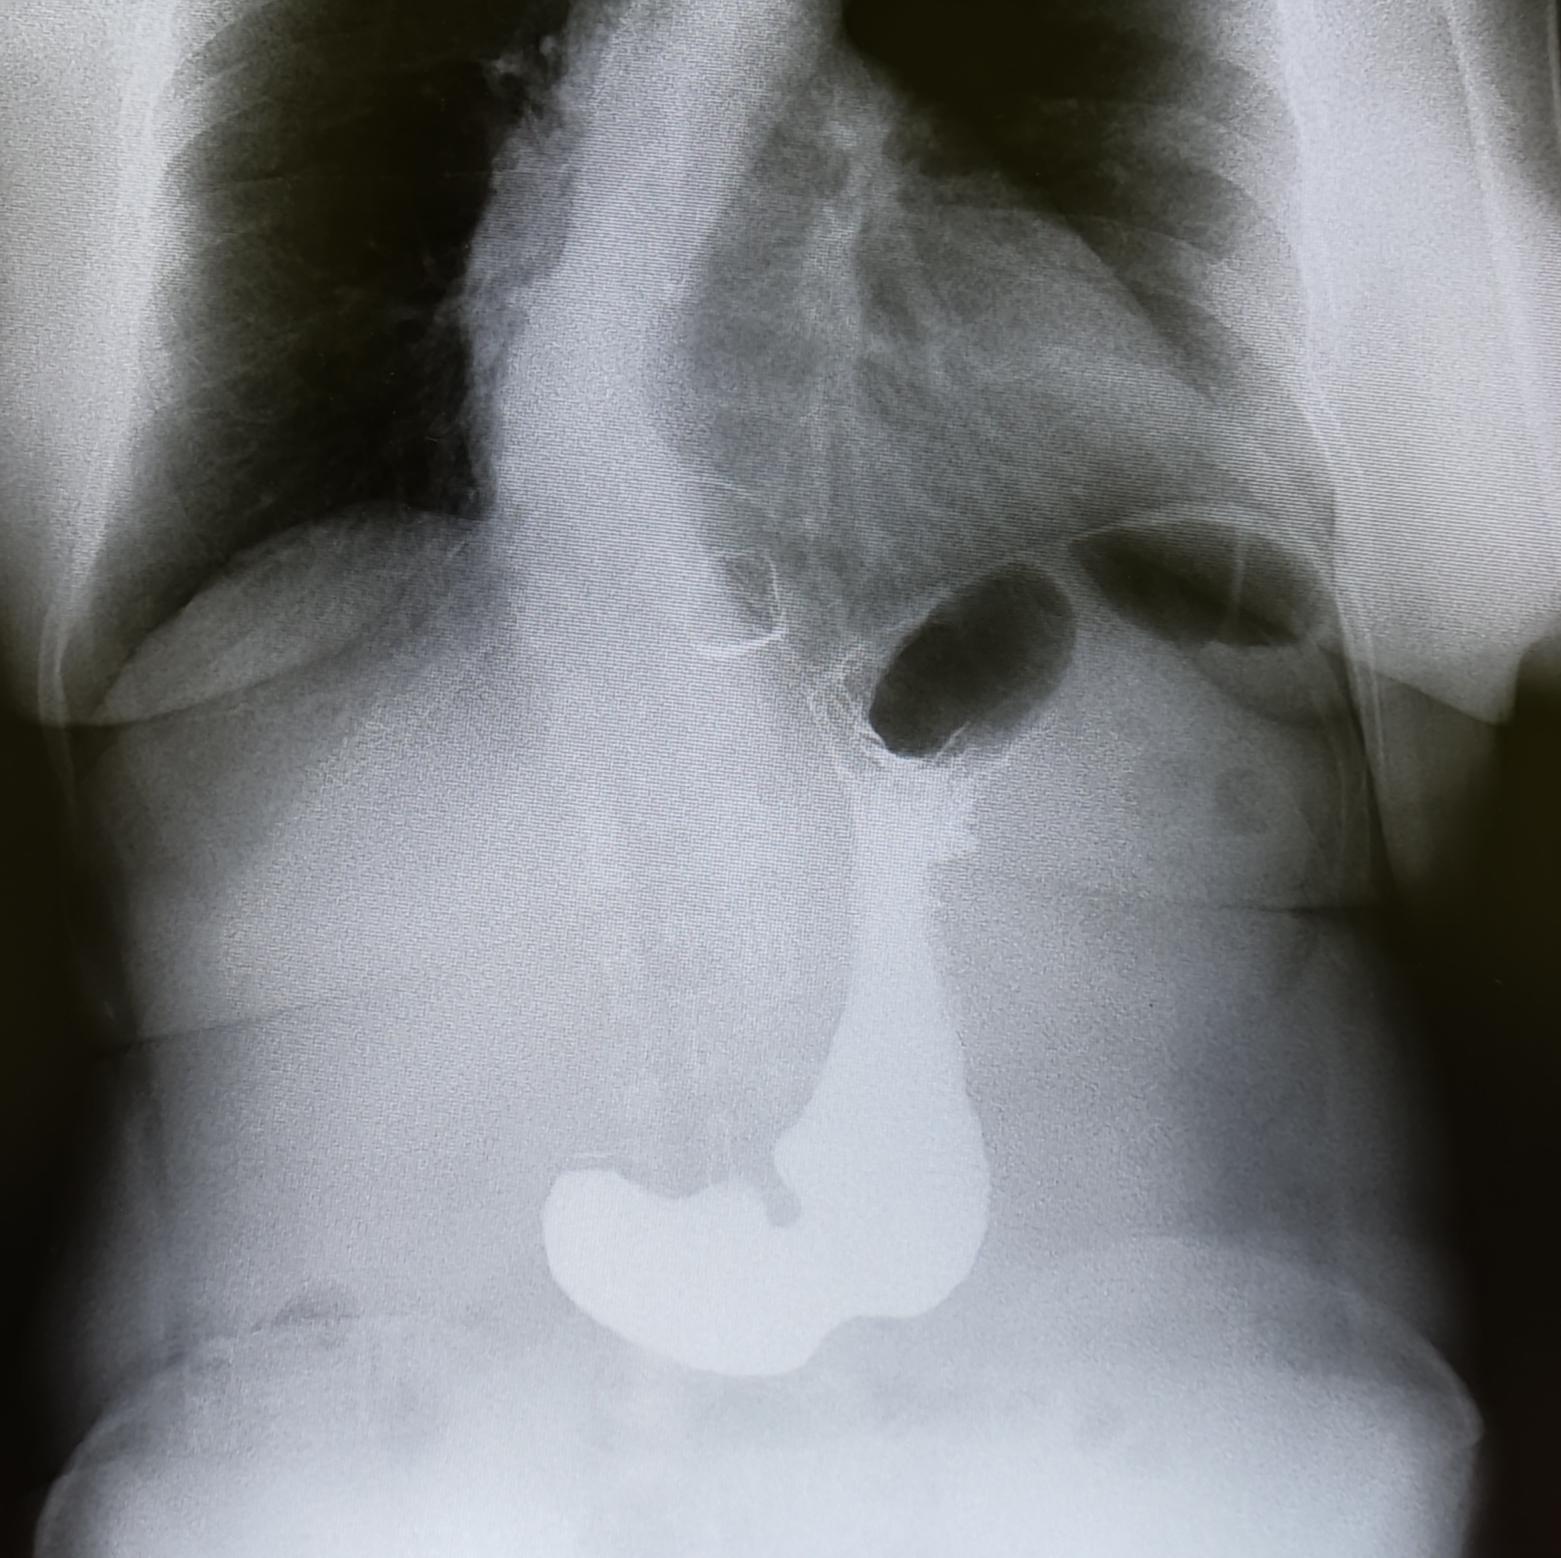

Диагностика ГПОД:ФГДС, МРТ ОБП, Рентгеноскопия желудка(для определения степени ГПОД-выполняется Р-скопия желудка в положении Тренделенбурга).

Описание: на рентгеноскопии желудка положении Тренделенбурга -над диафрагмой находится мешковидно расширенный брюшной сегмент пищевода, кардия расположена на уровне диафрагмы. Заключение: ГПОД 1ст